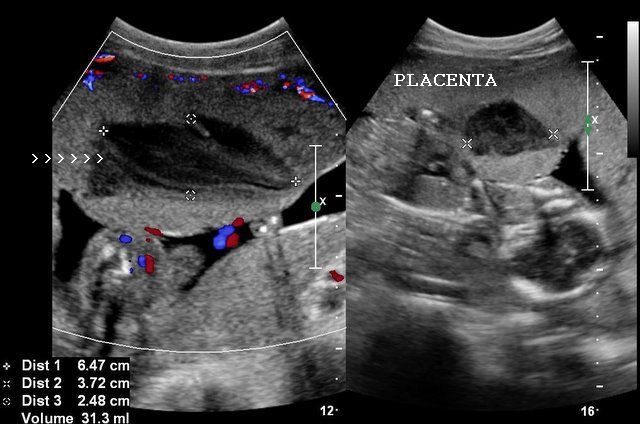

A trans abdominal image of the cervix and the lower edge of the placenta. Understand how the placenta works and the conditions that can affect the placenta during pregnancy. During this ultrasound a doctor will examine the fetus and. The first ultrasound to check the placenta is typically scheduled about the 18th to 20th week gestation.

A trans vaginal view of the placenta and cervix.